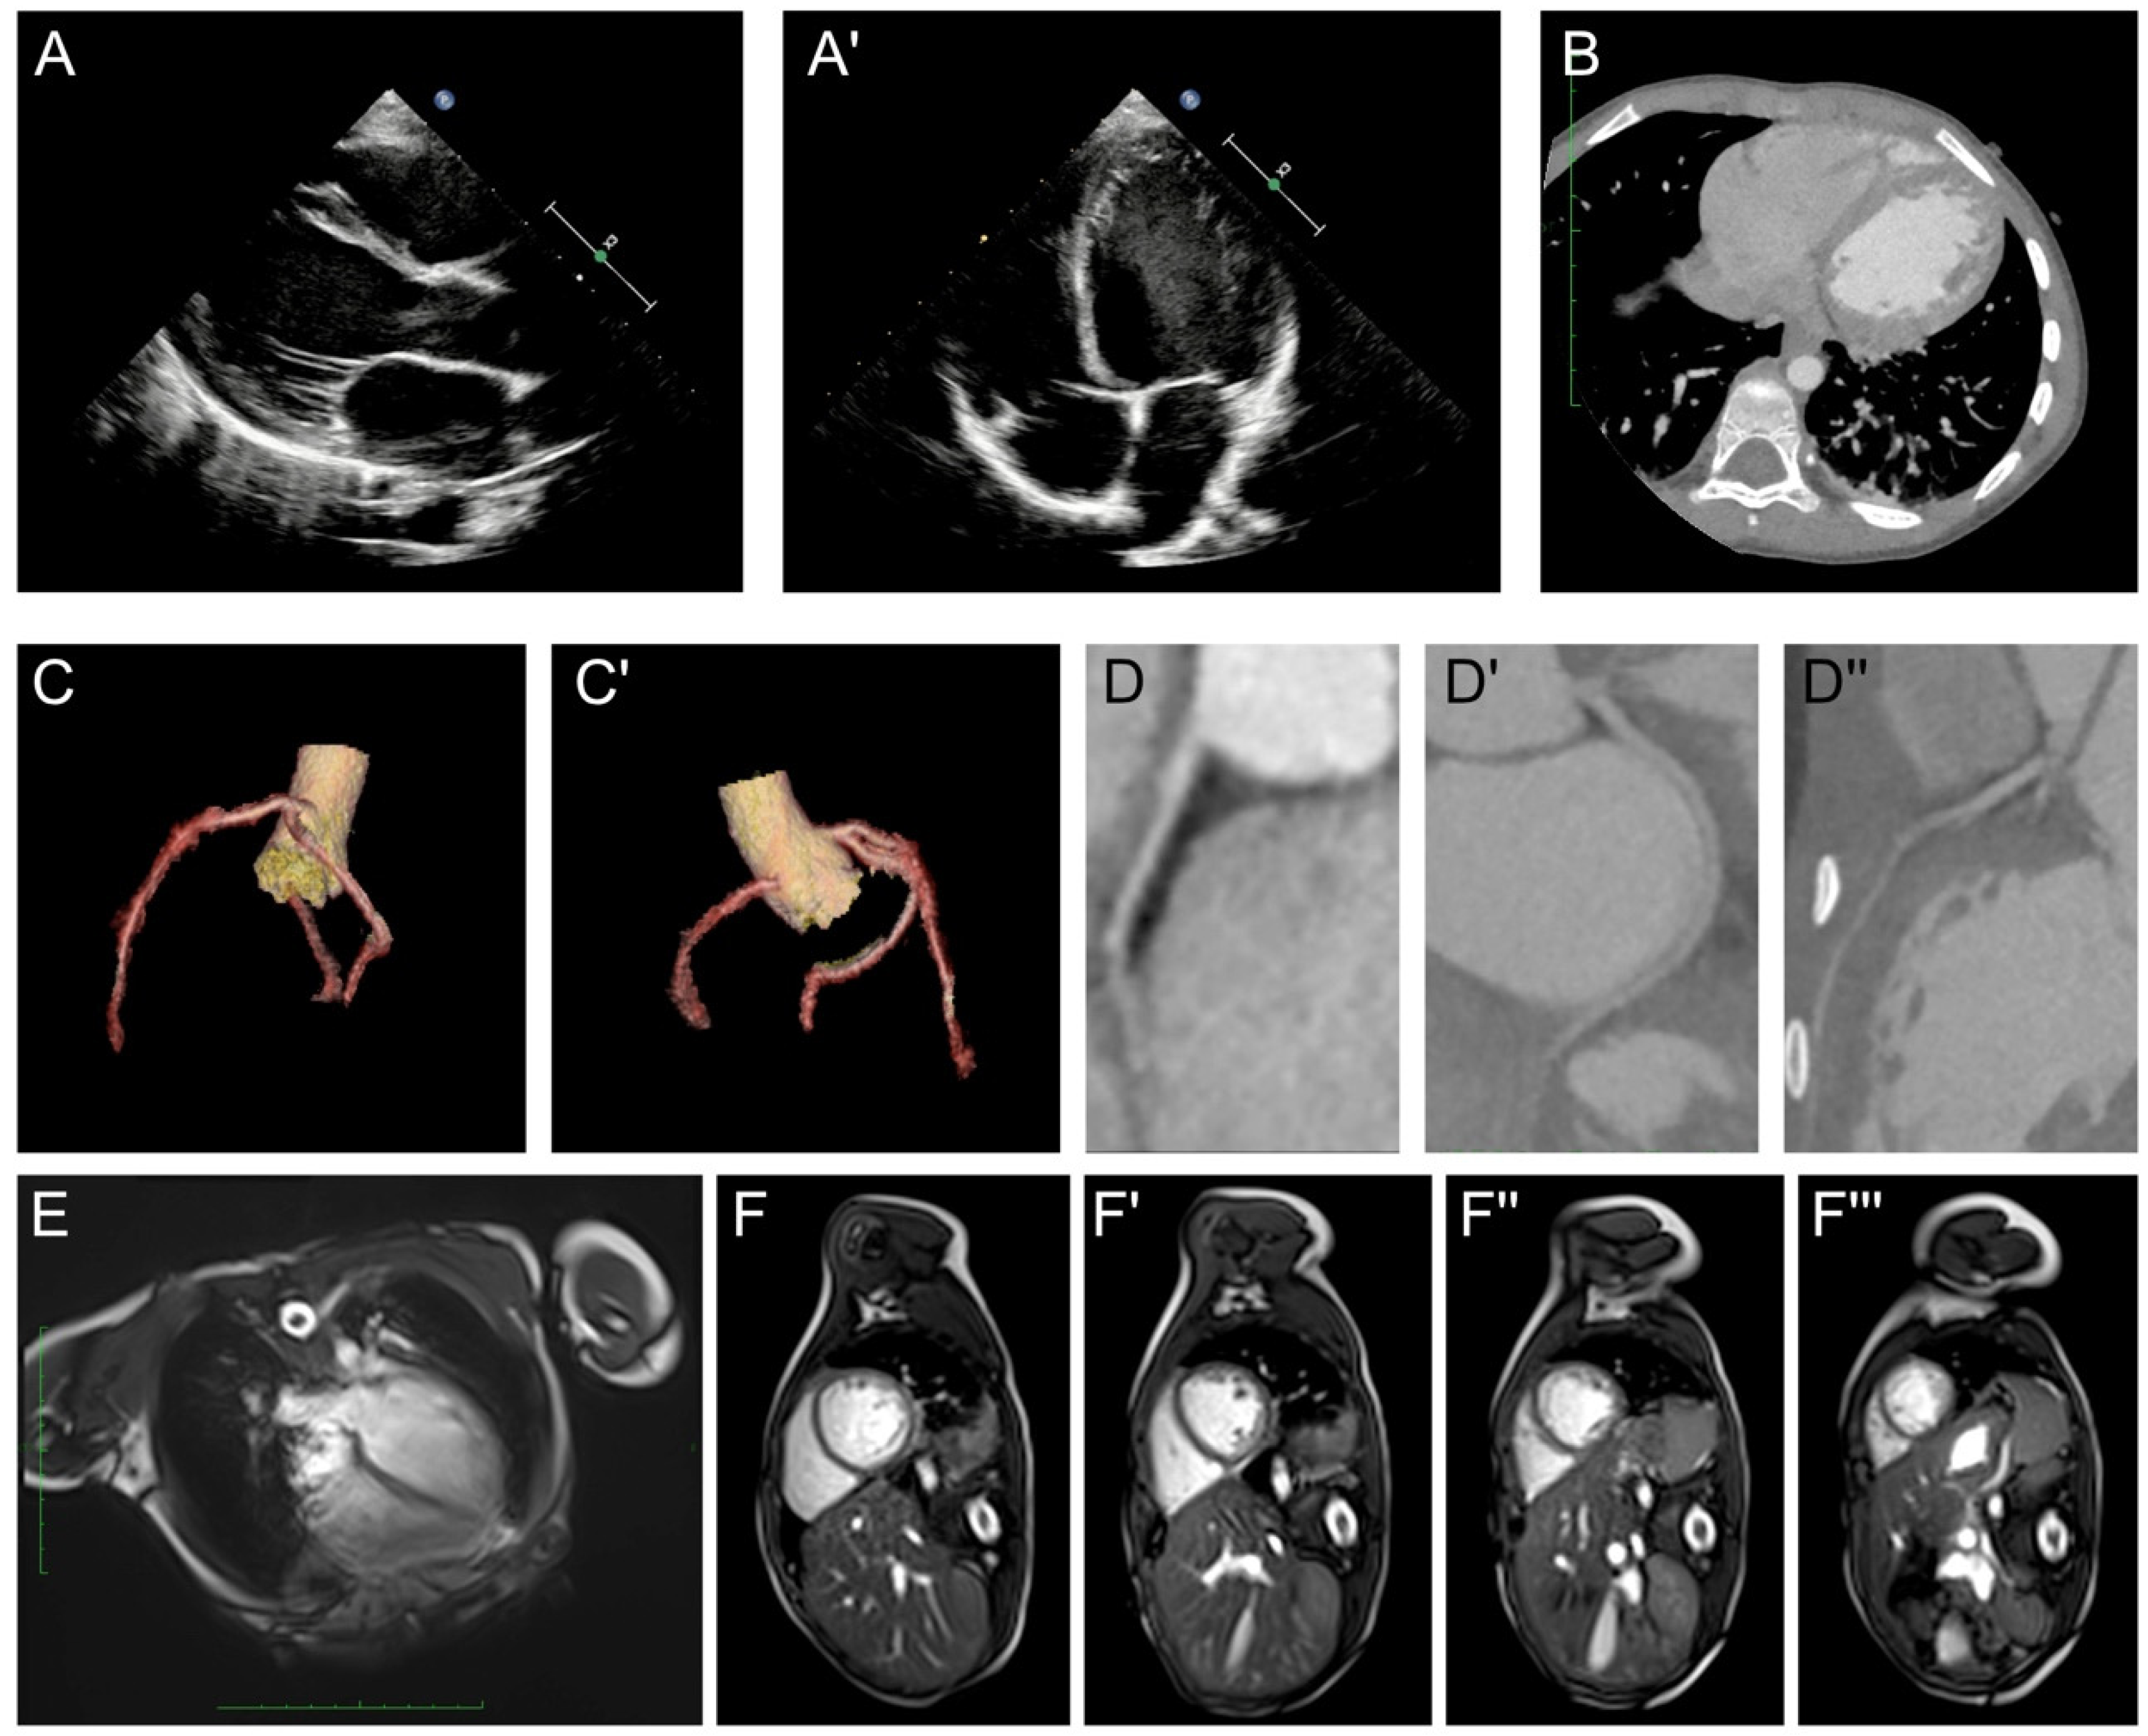

The initial laboratory results showed normal results for routine blood cell tests, blood gas analysis, hepatic and renal function. Elevation of B-type natriuretic peptide (139.65 pg/mL, n.v. <60 pg/mL) was observed, while the serum level of cTnI was within the normal range. Negative results were obtained for rheumatic screening, autoimmune antibodies, and thyroid function. Screening for potentially infectious viruses, including SARS-CoV-2, coxsackie virus, adenovirus, influenza virus, rhinovirus, and respiratory syncytial virus, all resulted in negative results. Electrocardiography (ECG) showed significant ST-T segment depression (II, III, aVF V3-V6 ST segment depression >0.05 mV with inverted T-waves, Figure 1A) and atrial (Figure 1B) and ventricular (Figure 1C) premature contractions were recorded with a Holter device. Additionally, the Prolonged QT interval is also reported. However, when recalculating the QTc using Bazett’s formula, it did not reach the criteria for long QT syndrome. Echocardiography revealed a dilated left ventricle (LVIDd = 48 mm, Z-score = 3.81, Figure 2A) with significant myocardial non-compaction (Figure 2A′), including a pseudotendon cord in the left ventricle. Chest computed tomography (CT) confirmed these findings of a dilated left ventricle and myocardial non-compaction (Figure 2B). A coronary artery CTA was performed, with images demonstrating normal structure and routine of the three branches of coronary arteries (Figure 2C,D). Cardiac magnetic resonance (CMR) showed an increased amount of left ventricular trabeculae, a dilated left ventricle (LVIDd = 47 mm), and a reduced ejection fraction (37.8%). The mass of the left ventricular myocardium was within the normal range (LV mass = 46.64 g, Z-score = −0.31), with no evidence of myocardial edema or significant fibrosis identified on the CMR examination (Figure 2E,F).

Figure 2. The proband’s clinical and radiographic manifestations. (A,A′) Echocardiography demonstrated an enlarged left ventricle (LVIDd = 48 mm, Z-score = 3.81) and myocardial non-compaction with a reduced ejection fraction. (B) Chest CT demonstrated the enlarged left ventricle and myocardial non-compaction. (C,C′,D,D′,D″) CTA demonstrated a standard structure and routine of three branches of coronary arteries. (E,F,F′,F″,F‴) CMR reported an increased amount of left ventricular trabeculae with enlarged left ventricle. No myocardial edema and significant fibrosis could be identified. LV indicated left ventricle.